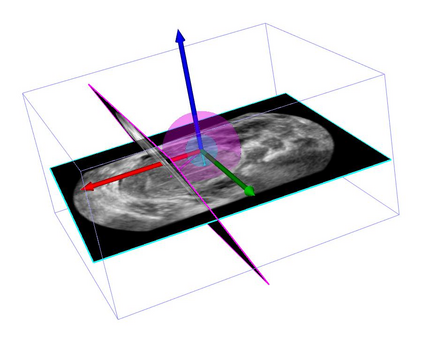

Standard plane (SP) localization is essential in routine clinical ultrasound (US) diagnosis. Compared to 2D US, 3D US can acquire multiple view planes in one scan and provide complete anatomy with the addition of coronal plane. However, manually navigating SPs in 3D US is laborious and biased due to the orientation variability and huge search space. In this study, we introduce a novel reinforcement learning (RL) framework for automatic SP localization in 3D US. Our contribution is three-fold. First, we formulate SP localization in 3D US as a tangent-point-based problem in RL to restructure the action space and significantly reduce the search space. Second, we design an auxiliary task learning strategy to enhance the model's ability to recognize subtle differences crossing Non-SPs and SPs in plane search. Finally, we propose a spatial-anatomical reward to effectively guide learning trajectories by exploiting spatial and anatomical information simultaneously. We explore the efficacy of our approach on localizing four SPs on uterus and fetal brain datasets. The experiments indicate that our approach achieves a high localization accuracy as well as robust performance.